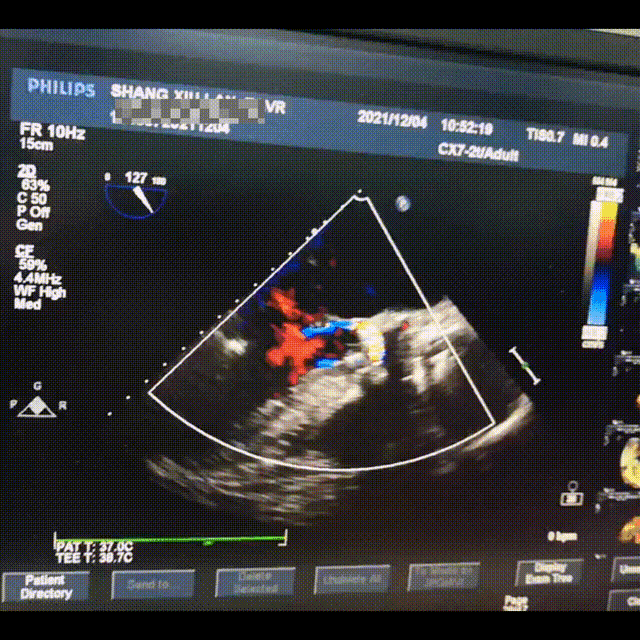

瓣膜释放后形态位置良好,造影几乎无瓣周漏

术后超声微量瓣周漏

跨瓣压差3mmHg